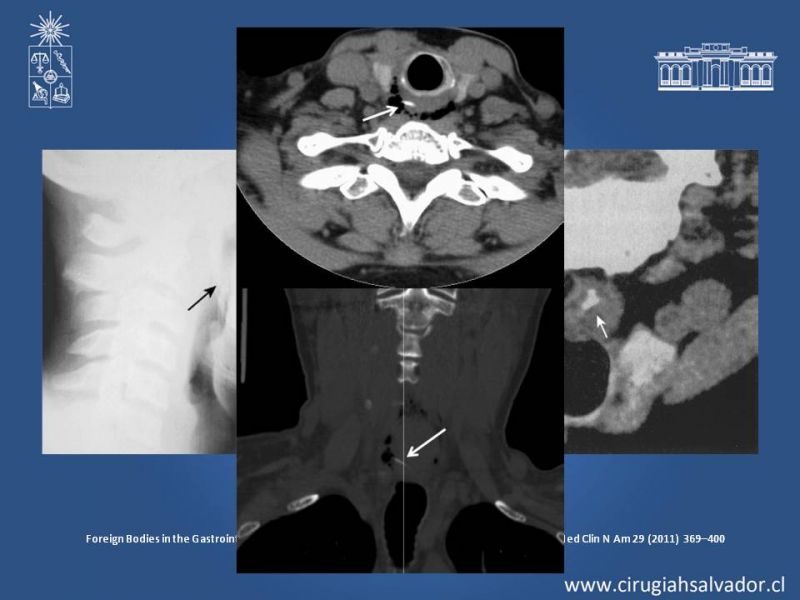

Cuerpo Extraño Esofágico

Digestivo Alto